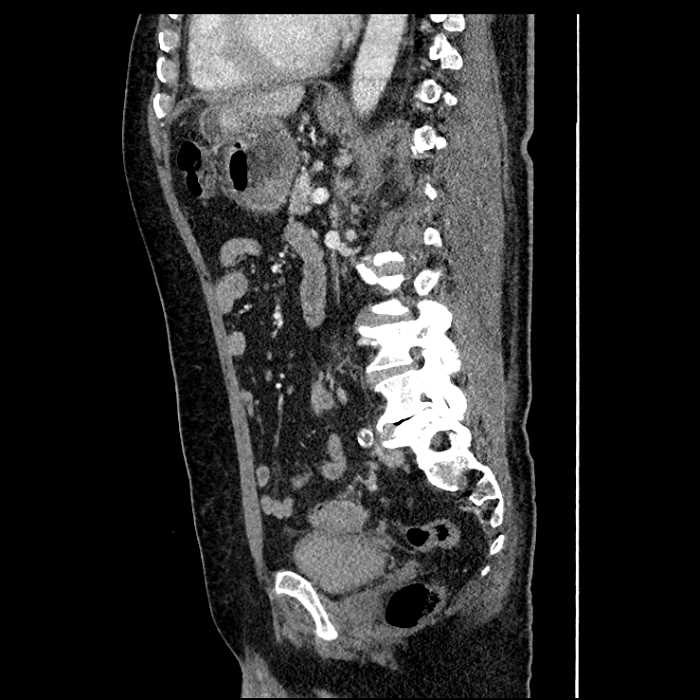

• Mild mural thickening of a segment of the sigmoid colon with adjacent fat stranding and a 1.5 cm fluid and gas collection along the tip of an inflamed diverticulum

• Loss of the normal fat plane between this collection and adjacent loops of small bowel, which demonstrate mural thickening

• No bowel obstruction

Acute sigmoid diverticulitis complicated by a small contained perforation and a large abscess in the right hepatic lobe. Additional small subcapsular abscesses along the anterior margin of the left hepatic lobe.

Additionally, loss of the normal fat plane between the peridiverticular collection and adjacent thickened loops of small bowel raises the potential for an enterocolonic fistula.

Hepatic abscess showing the double target sign with low density internally surrounded by a thin inner enhancing rim (red arrow) and ill-defined outer low density rim (yellow arrow). Blue arrow indicates an internal septation. Red arrows: additional smaller subcapsular abscesses. Red arrow: focal contained perforation associated with diverticulitis.